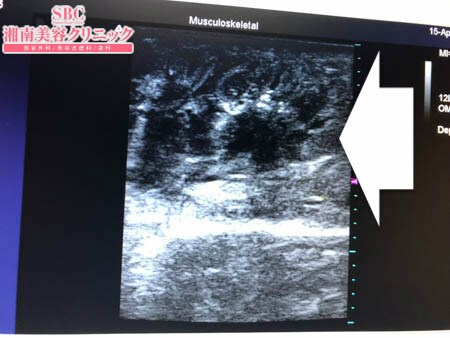

No.236347【脂肪吸引】【動画あり】湘南美容外科脂肪吸引最高責任者である竹田先生による脂肪吸引のフォトギャラリー!大阪からご来院!脂肪吸引は竹田先生以外に考えられないです!術中3Dタッチビュー・右二の腕

今回は二の腕全周の脂肪吸引を

ご用命いただきましたので

その術中変化を紹介したいと思います。